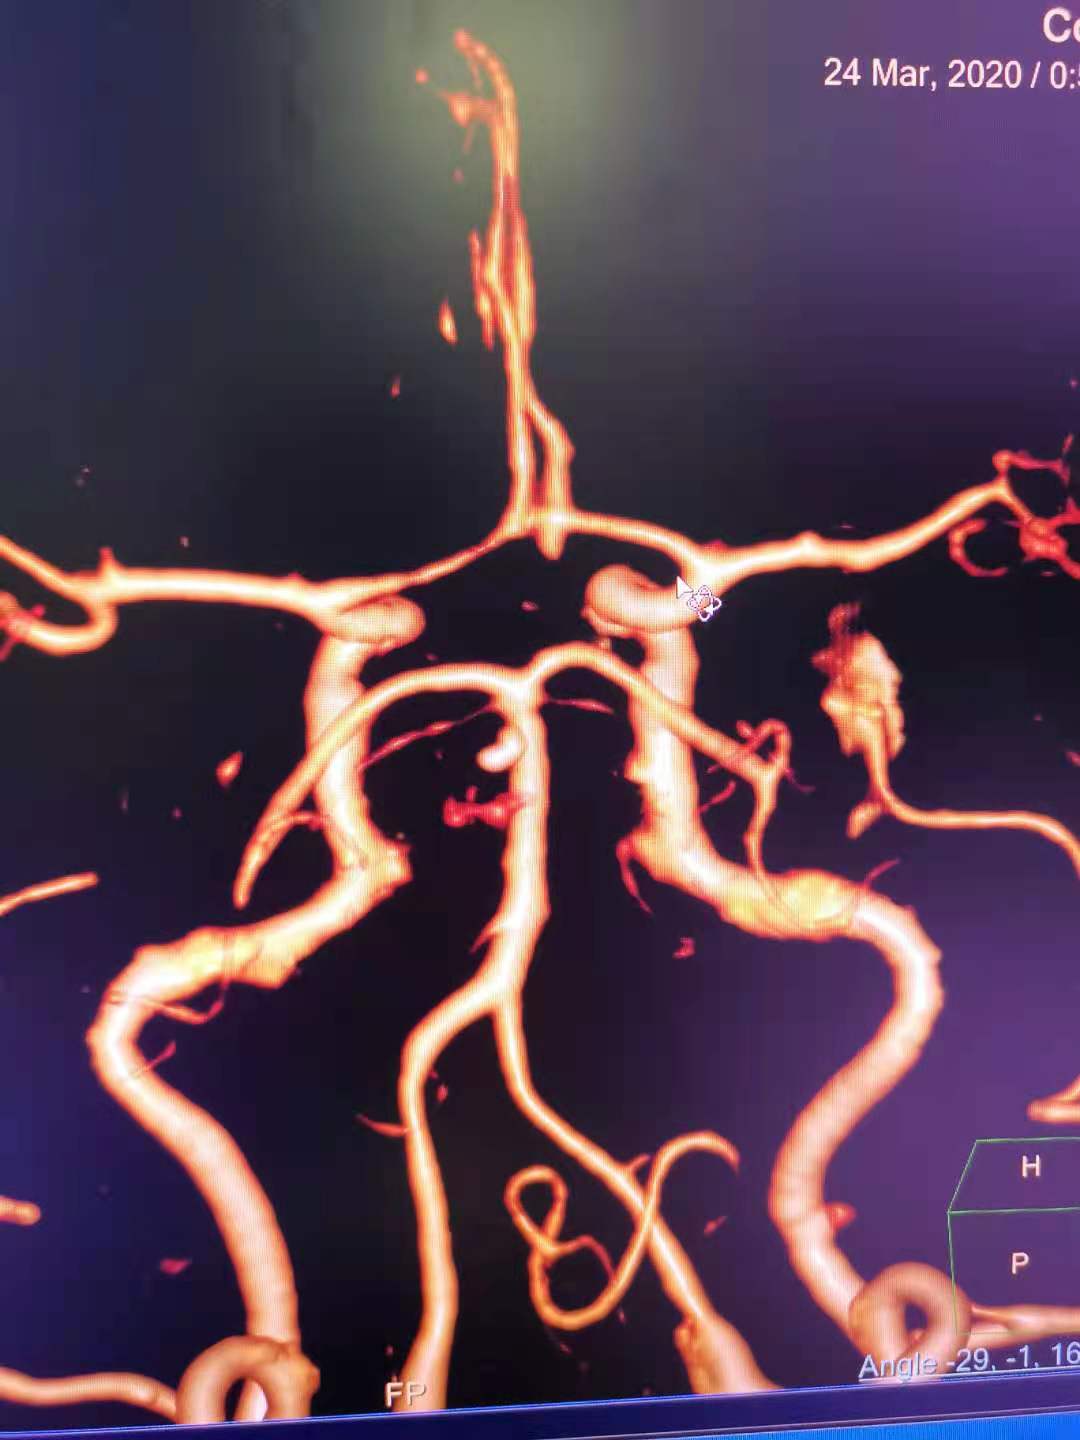

CTA 结果

本次⼊院⾏DSA检查:PICA供⾎区有畸形⾎管团,引流到横窦

术后CTA显⽰

术后CTA显⽰:畸形⾎管团消失